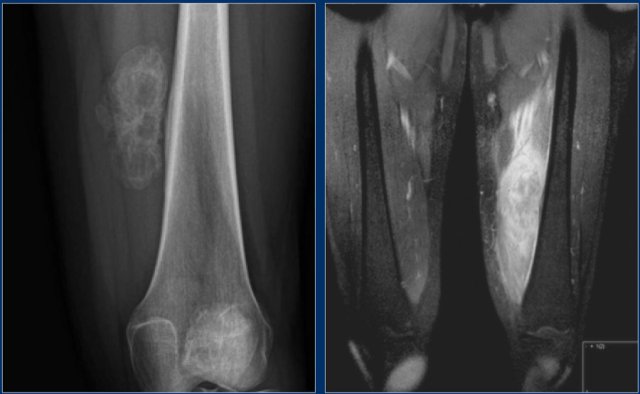

Plain radiograph and coronal T1-weighted contrast-enhanced fat-suppressed MR image of a mixed lytic and sclerotic lesion of the distal femoral diaphysis.

Notice the homogeneous thickening of the cortical bone.

There are no calcifications.

The MR image shows that the lesion has lobulated contours and nodular enhancement.

The homogeneous enhancement in the upper part with edema and cortical thickening are not typical for a low-grade chondrosarcoma.

A high grade chondrosarcoma must be considered in the differential diagnosis.

Biopsy revealed dedifferentiated chondrosarcoma.